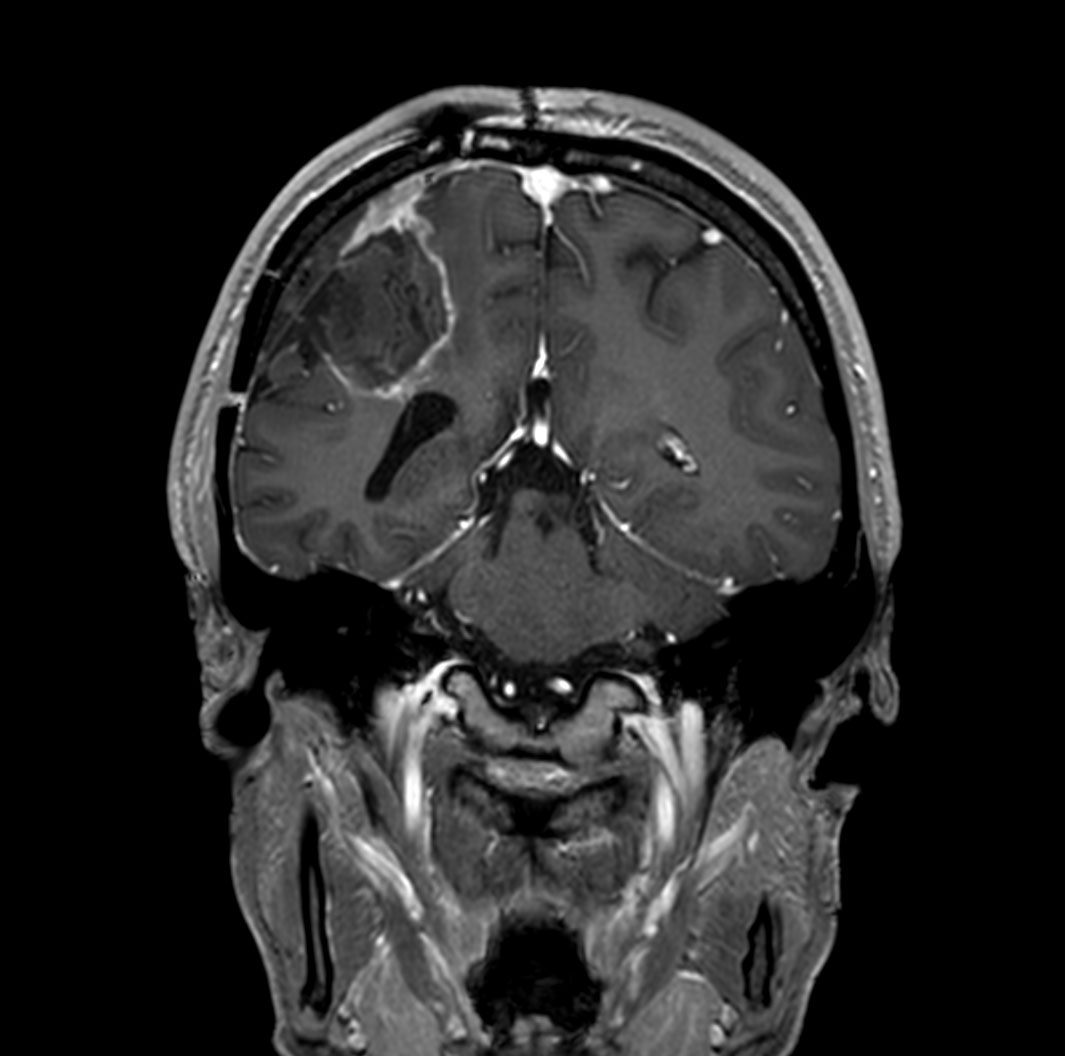

T1w 3D FFE with gado (coronal reformat)